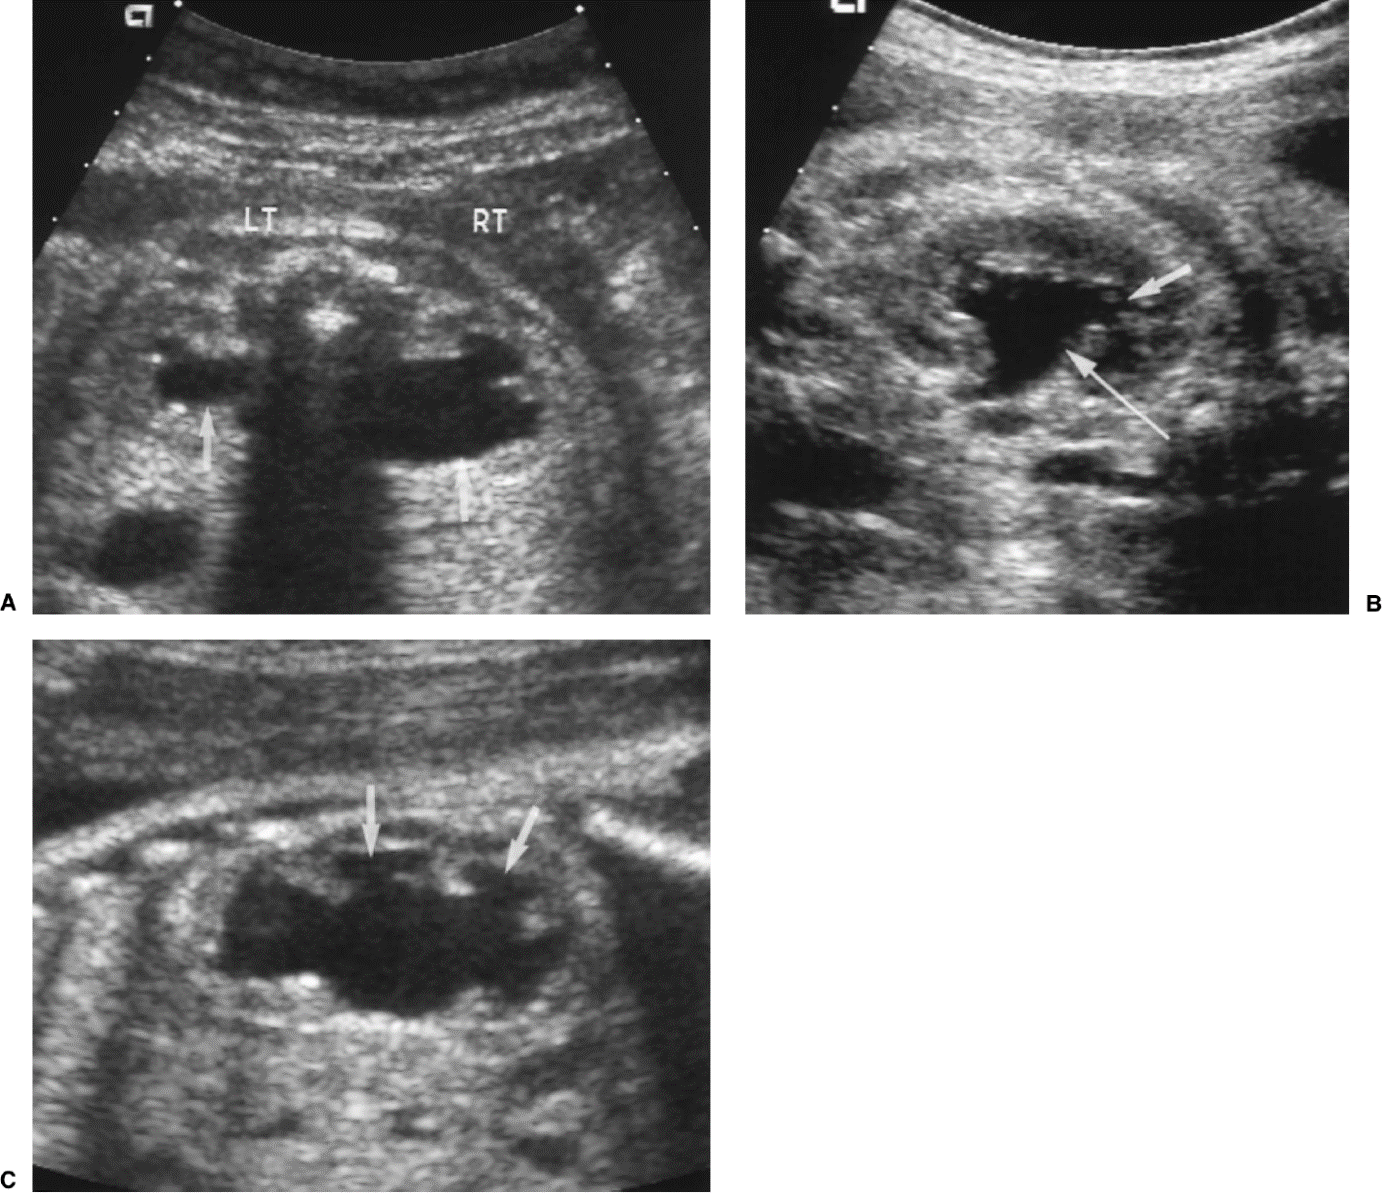

Links normale situatie: 1 nier, 2 nierbekken, 3 urineleider, 4 blaas, 5 overgang van urineleider in blaas, 6 plasbuis.

Rechts situatie zoals die bij urethrakleppen kan ontstaan: Verwijding van de nieren, het nierbekken en de urineleider. De urineleider wordt niet alleen wijder in de breedte maar ook in de lengte zodat en geslingerd verloop ontstaat. De blaas is zeer gespierd geworden en daardoor dikwandig en kartelig. De blaasuitgang is ook zeer gespierd en daardoor vernauwd. Het eerste deel van de plasbuis is verwijd tot aan de urethrakleppen. De blauwe pijl wijst naar de plaats van de urethrakleppen. Door de gespierde blaaswand wordt de urineleider die links in het plaatje zichtbaar is (dat is aan de rechter zijde van het kind) vernauwd waardoor de urineleider stroomopwaarts nóg meer verwijding vertoont. Aan de rechter zijde is de klep tussen urineleider en blaas beschadigd geraakt. De inmonding van de urineleider in de blaas is een wijde opening waardoor urine direct weer vanuit de blaas naar de nier kan stromen (Groene pijl)

Normale plasbuis voorbij de kleppen

Plaats van de urethrakleppen

Verwijd eerste deel van de plasbuis tot aan de kleppen

Kleine, kramperige blaas met kartelige contour veroorzaakt door uitstulpingen van de blaaswand (divertikels)

Terugstroom van urine tot in de nier (vesico-ureterale reflux) en verwijde urineleider

Plasfoto met contrastmiddel (mictie cystogram)